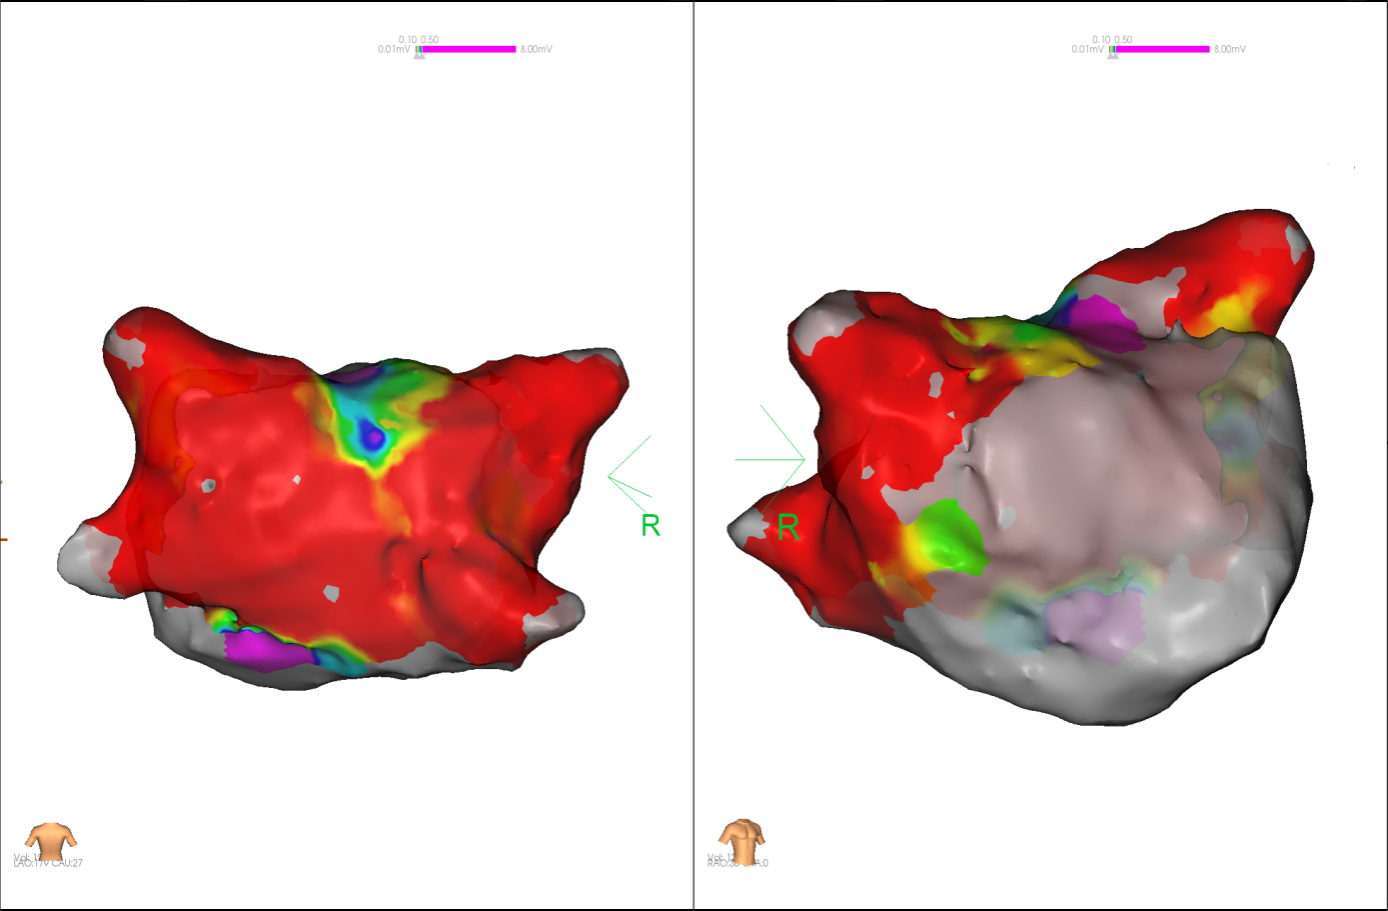

经充分术前评估及准备后,该患者手术在抗心衰药物持续静脉泵入、高流量吸氧支持下及麻醉、护理团队的通力配合下进行,由薛建颖、崔明亮主治医师具体实施。术中通过右侧股静脉送入心腔内超声至右心房,排除左房血栓后成功指导房间隔穿刺,沿可调弯鞘管送入锦江心脏脉冲电场消融导管至左房,构建左房三维解剖模型并行基质标测,标测显示左房基质差,分别行左侧、右侧肺静脉及后壁BOX消融。消融参数:1800v,400ms,400μs,共放电消融140次(消融右肺静脉时转复为窦性心律),验证双肺静脉均隔离。术后重新标测显示所有肺静脉均已急性阻滞,消融效果理想,肺静脉前庭损伤范围也达到了预期的标准,同时心腔内超声监测未见明显心包积液。手术仅用时30分钟,时间明显缩短,手术过程精准高效。术后患者恢复情况良好,维持窦性心律。

图2 术中电压标测提示左房基质差

图4 消融前后基质标测提示肺静脉消融效果明显